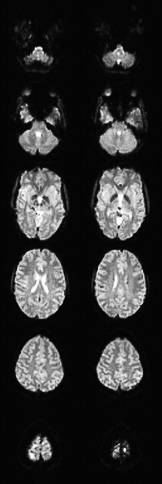

The device has allowed Princeton neuroscientists to conduct a wide array of pioneering experiments, ranging from some of the most detailed studies of the brain's visual system ever to be carried out in a human, to the first studies of characteristically human faculties such as moral reasoning and economic decision-making.

The center has also integrated the MRI with other forms of real-time sensing that track eye motion and changes in the skin. Observing these other types of responses permit a more comprehensive understanding of how the brain reacts to the world.